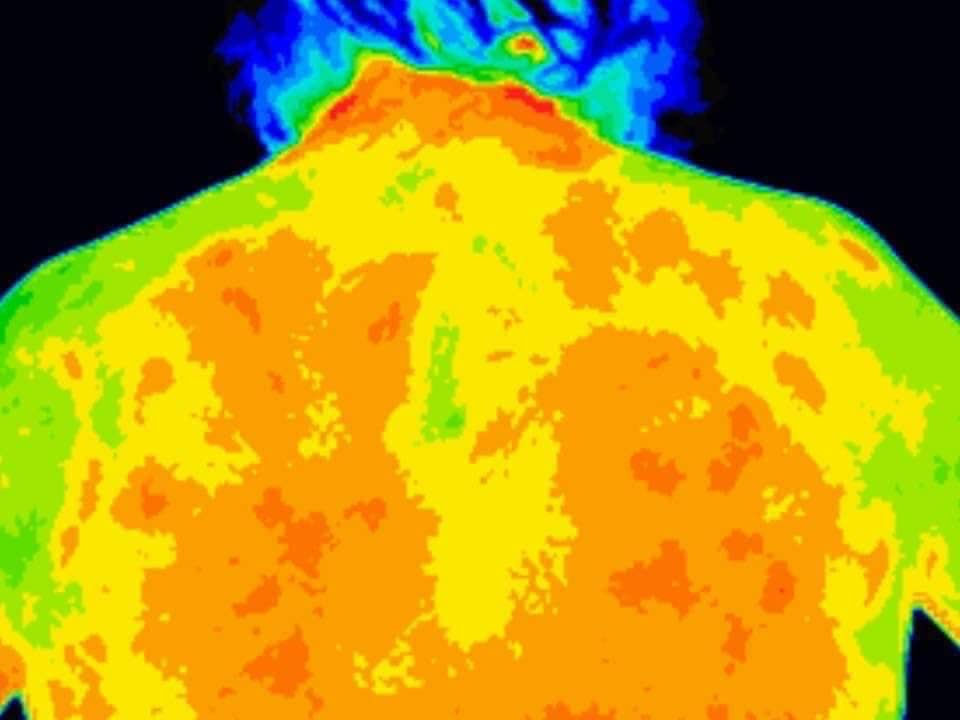

Here is my November 2018 and my March 2019 thermagrams from my back.

The red is the inflammation. Wow what a difference."